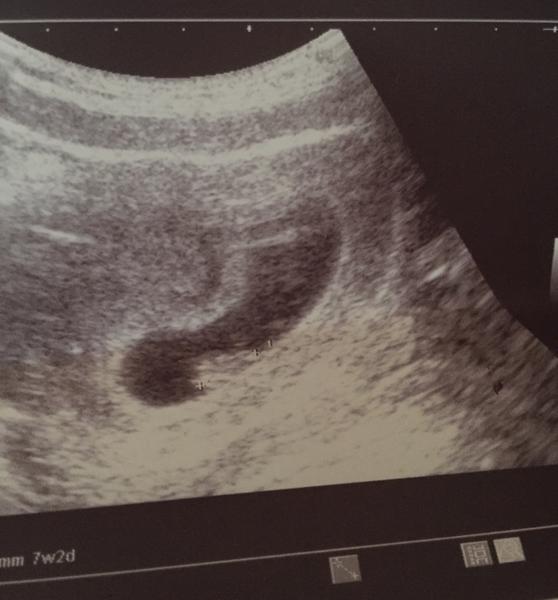

Ultrazvuk. Kolikátý týden podle utz bych mohla být?

Na fotce máš napsáno dole 7+2 tt